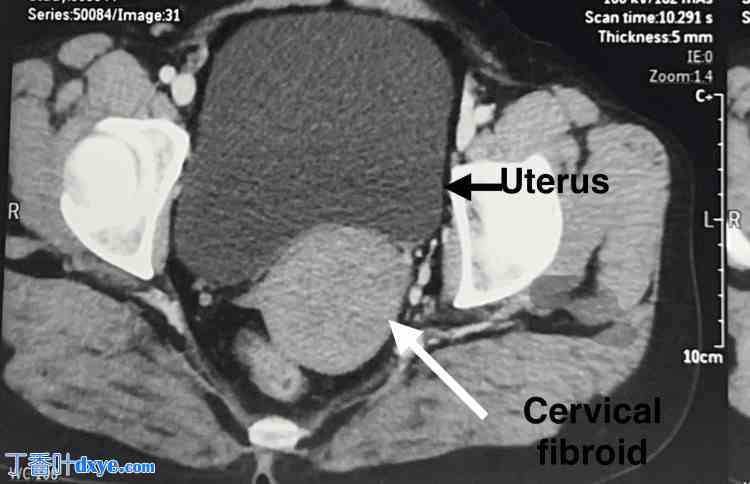

一名35岁、既往有正常分娩史(孕1产1)的女性,因月经过多就诊于院。她无任何压迫症状。腹部柔软,无压痛,未触及腹盆腔肿块。阴道窥器检查发现宫颈前唇增厚,宫颈后唇变薄并覆盖于肿块之上。双合诊检查发现宫颈前部触及一8×7 cm肿块,向上延伸至子宫体部,上缘未触及。超声检查显示子宫前倾,子宫内膜厚度为7.5 mm。如图1所示,在子宫体下部和宫颈处发现一边界清晰的异质回声病灶,大小为6.7 x 7.4 x 7.2 cm(约180 cc),可能为子宫肌瘤。

图1. 超声图像显示子宫体下部和宫颈处有一边界清晰的异质回声病灶,大小为6.7 x 7.4 x 7.2 cm(约180 cc),可能为较大的宫颈肌瘤。